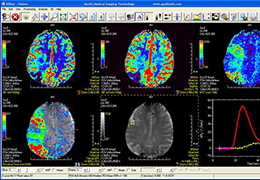

View X-Ray CT & MRI Scans Fast and Easily

Designed for surgeons, Pro Surgical 3D makes it easy to view patient scans quickly. Pro Surgical 3D facilitates the optimal 3D treatment and assessment workflows based on X-ray CT and MRI scans – and best of all, it’s FREE!

Designed mainly for CT and MR DICOM modalities.

Performs 3D reconstruction and volume rendering.

Multi-planar slicing.